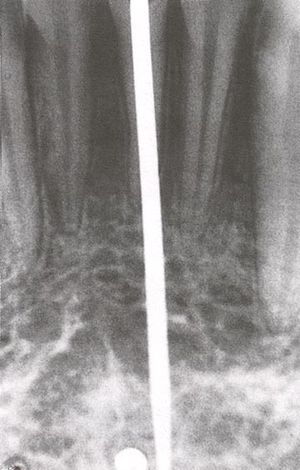

قبل زراعة الأسنان، يطلب من المريض اجراء فحص تصوير للأسنان، وعادة يطلب اجراء صورة خاصة (صورة أشعة بانوراما للأسنان) أو حتى فحص التصوير المقطعي المحوسب (CT)، للكشف والتشخيص عن حالات الأسنان التي ليس بالامكان رؤيتها من خلال الفحص الاعتيادي.

في النوع الأول تمر الغرسة العصوية الشكل عبر قناة بعد توسيعها، لتتجاوز ذروتها وتنغرز في عظم الفك فتثبت السن إلى العظم إن كانت متحركة.

استخدم هذا النوع على شكل غرسة أسطوانية من معدن التيتان ذات ثقوب تنتهي في الأعلى بمهماز وهي مفتوحة من الأسفل ومطلية بجزيئات التيتان التي يقذف بها سطح الغرسة، ثم تحمى في حرارة عالية، فتتماسك الجزيئات مشكلة سطحاً خشناً يحمل تجاويف ونواتئ تساعد على الاشتباك بالعظم.

تستعمل سنبلة خاصة أسطوانية لتفريغ العظم بشكل يناسب الغرسة، ويشترط في هذه الطريقة اتباع الأمور التالية:

أن يفرغ العظم بشكل أسطوانة، ويترك العظم في مركز الأسطوانة سليماً وأن ينخفض سطح الغرسة الخارجي عن سطح العظم المغروسة فيه مسافة 5 - 8 مم ولا يجوز بأي حال أن يبرز مهماز الغرسة في منطقةٍ غشاؤها المخاطي متحرك، ويجب أن تكون دائماً في منطقة مغطاة بغشاء مخاطي متقرن.

تكون الغرسة وحيدة الأسطوانة أو ثنائيتها أو ثلاثيتها، وقد جربت هذه الغرسات مدة عام، ثم أجريت دراسة مجهرية على الفك والعظم المحيط بالغرسة، فتبين وجود التصاق كامل بين العظم والسطح المطلي بجزيئات التيتان، كما تبين وجود تشكلات عظمية في الفجوات الموجودة على محيط الأسطوانة المغروسة.